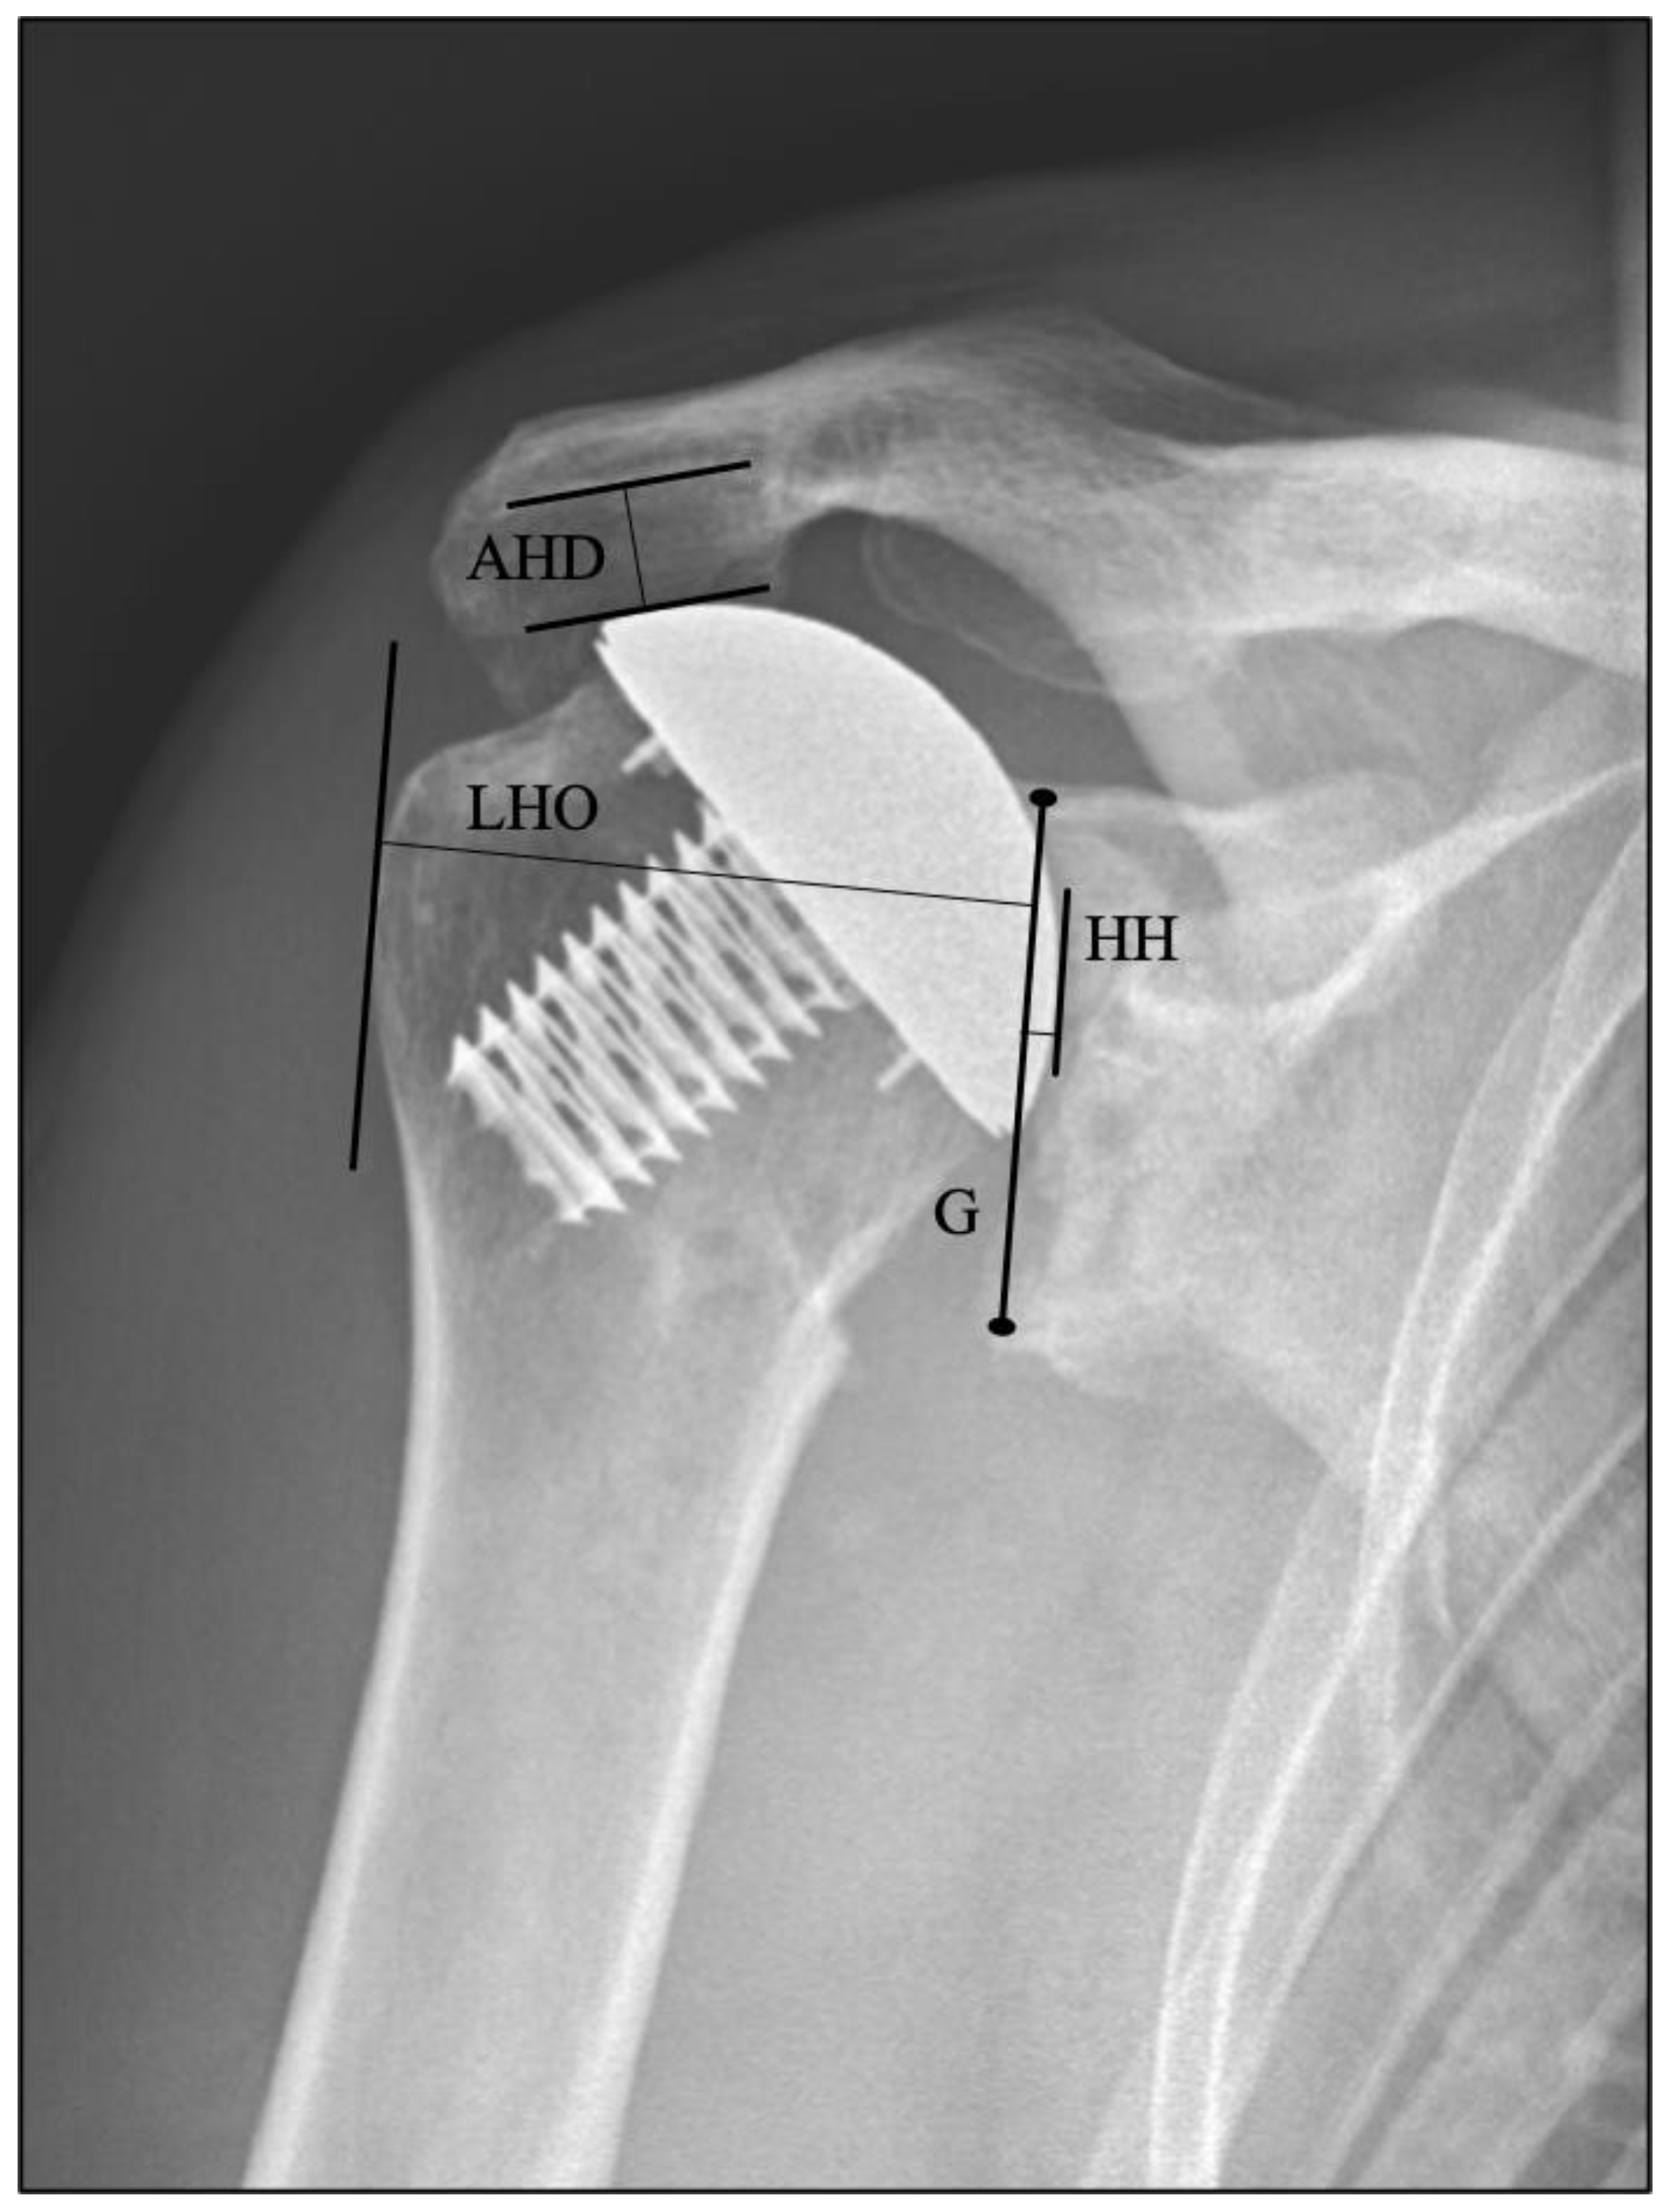

2.4. Clinical and Radiological Evaluations

| Radiographic Parameter | Six Months | One Year | Two Years | Five Years | p-Value (Two Years vs. Six Months) | p-Value (Five Years vs. Six Months) |

|---|---|---|---|---|---|---|

| Acromiohumeral distance (mm) | 12.7 (0.3) | 12.5 (0.3) | 12.1 (0.3) | 10.4 (0.4) | 0.17 | <0.001 |

| Lateral humeral offset (mm) | 52 (0.3) | 51.9 (0.3) | 51.5 (0.3) | 50.5 (0.4) | 0.02 | <0.001 |

| Joint gap width (mm) | 2.9 (0.1) | 2.8 (0.1) | 2.6 (0.1) | 1.4 (0.2) | 0.17 | <0.001 |

| Franklin radiolucency grade | 2.2 (0.1) | 2.7 (0.1) | 3.1 (0.1) | 3.8 (0.1) | <0.001 | <0.001 |